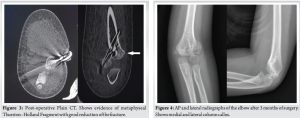

Under general anesthesia and in a supine position, closed reduction was done with longitudinal traction, mediolateral correction, and elbow flexion to stabilize the fracture. We did percutaneous pinning with two lateral 1.5 mm K-wires. We did arthrography by injecting Iohexol from the lateral aspect of the elbow. The arthrogram showed articular congruity (Fig. 2). Pins were bent, cut, left outside for easy removal, and immobilized at seventy degrees with a back slab. We did a post-operative CT to assess the fracture pattern and reduction. (Fig. 3).

In inconclusive cases or suspected capitellum or intercondylar fractures, we can perform a CT or MRI or ultrasonography preoperatively or arthrogram intraoperatively. In transphyseal separations, CT can help identify the Thurston–Holland fragment. In our case, the CT showed a large medial Thurston-Holland fragment, a feature suggestive of entire distal humeral physeal injury, differentiating it from lateral condyle fracture. MRI is useful in differentiating these injuries accurately, but it needs sedation. Ultrasound is helpful in transphyseal separation of infants where the ossification of the lateral epiphysis has not started [1]. Treatment: Arthrography helps differentiate transphyseal separation and Type 3 Weiss lateral condyle fracture. It is a common conception to general orthopedic surgeons that lateral condyle requires open reduction. However, some lateral condyle humerus may be amenable for closed reduction. Hence, arthrogram is necessary during the surgery [6,7]. The continuous articular margin on the arthrogram suggests transphyseal separations, type 1, 2, or well-reduced type 3 Weiss lateral condyle fractures [8]. Type 3 Weiss fractures with displacement of more than 2 mm, even after closed reduction, need open reduction and pinning or cannulated cancellous screws [9]. A transverse column pin adds stability to the two lateral pins for lateral condyle fractures. Transphyseal separations can be treated similarly to supracondylar fractures with two to three lateral or cross wires [2]. Postoperatively, periosteal new bone formation is also an indicator of the type of fracture. The lateral condyle has a callus predominantly on the lateral column, and transphyseal separations have a callus on both medial and lateral columns. The flowchart (Fig. 5) can help in management.